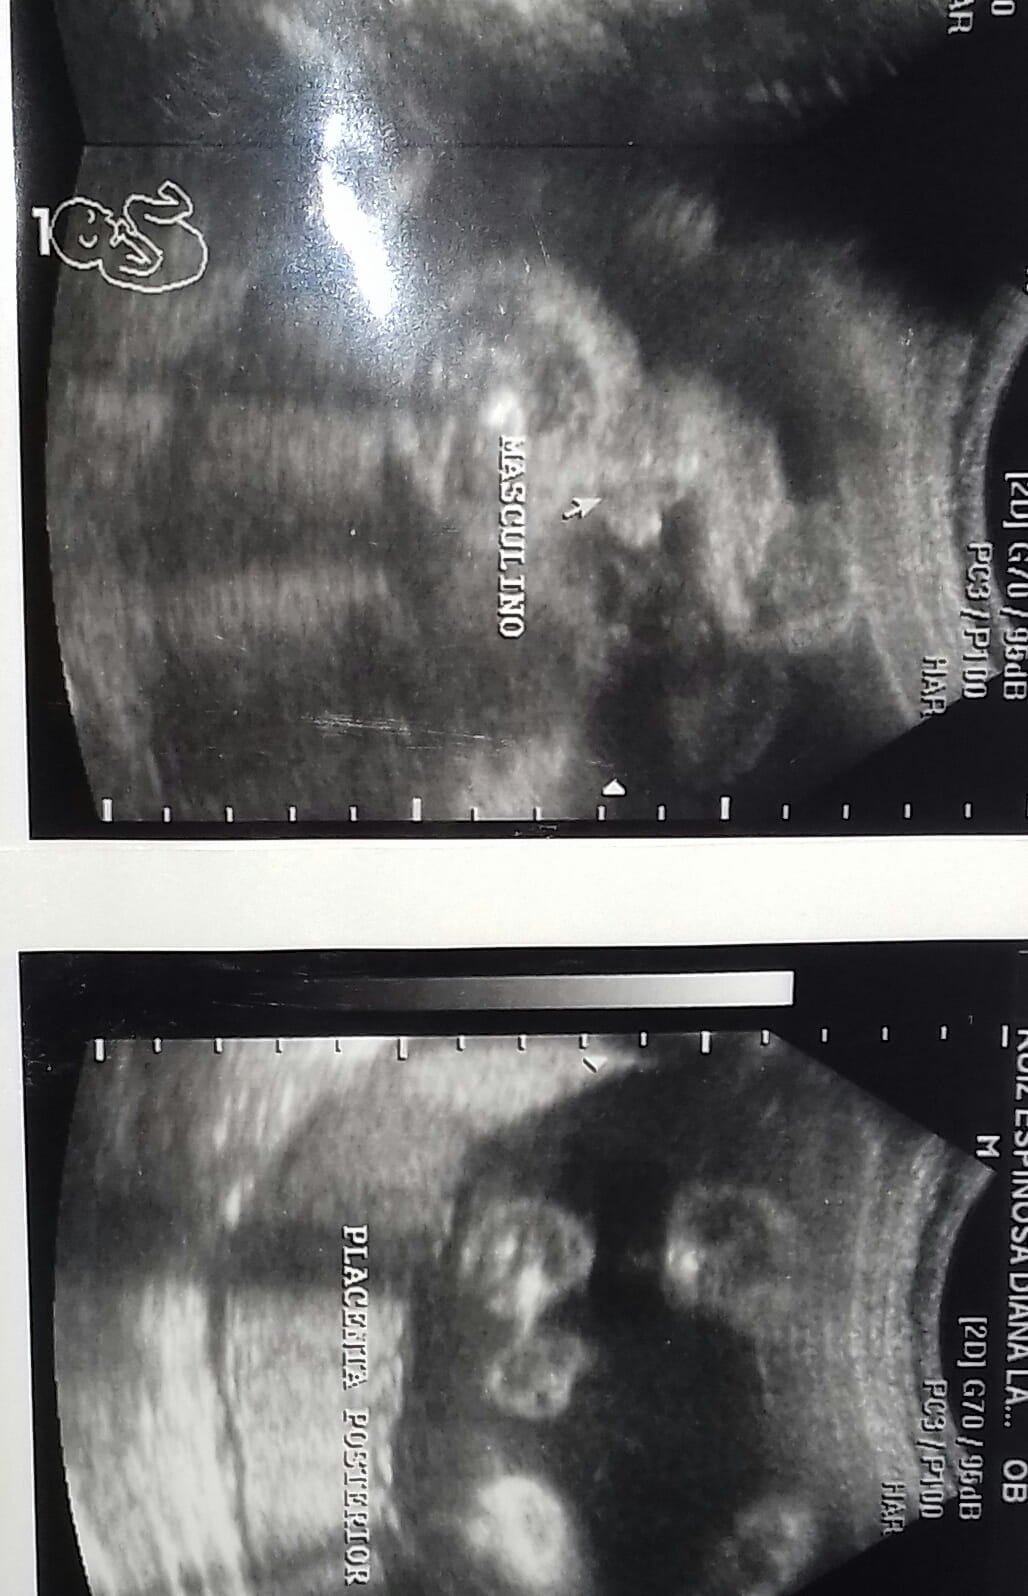

Hoy fui hacerme un ultrasonido tengo 25 semanas con 6 dias Y me dijeron el sexo del bebe Que sera Niño, La verdad yo deseaba tanto una niña todos me decian que seria Niña y ahora me dijeron que es Niñl de igual manera estoy Feliz por que esta sanito❤ pero Mi pregunta es, ¿Puede ver algun error del sexo?

Es niño...si te dicen que es niña puede ser que sea un error y sea niño...pero cuando se ve ¨niño¨ dificilmente será un error.